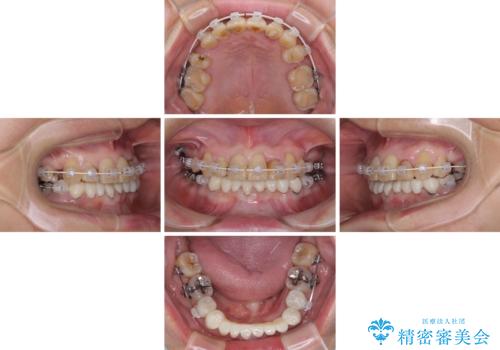

- 常に外れている下顎のブリッジと、前歯のデコボコと色を気にして来院された患者様です。

前歯のデコボコおよび奥歯の咬み合わせを改善するために、上顎左右の小臼歯を欠損スペースを利用して歯列を整え、矯正治療後に気になる上下前歯などをオールセラミッククラウンで美しく仕上げていくこととしました。

色や歯列が整ったことはもちろん満足いただけましたが、上顎の舌側転位していた前歯が綺麗に整ったことで違和感が減ったことを非常に喜んでいらっしゃいました。